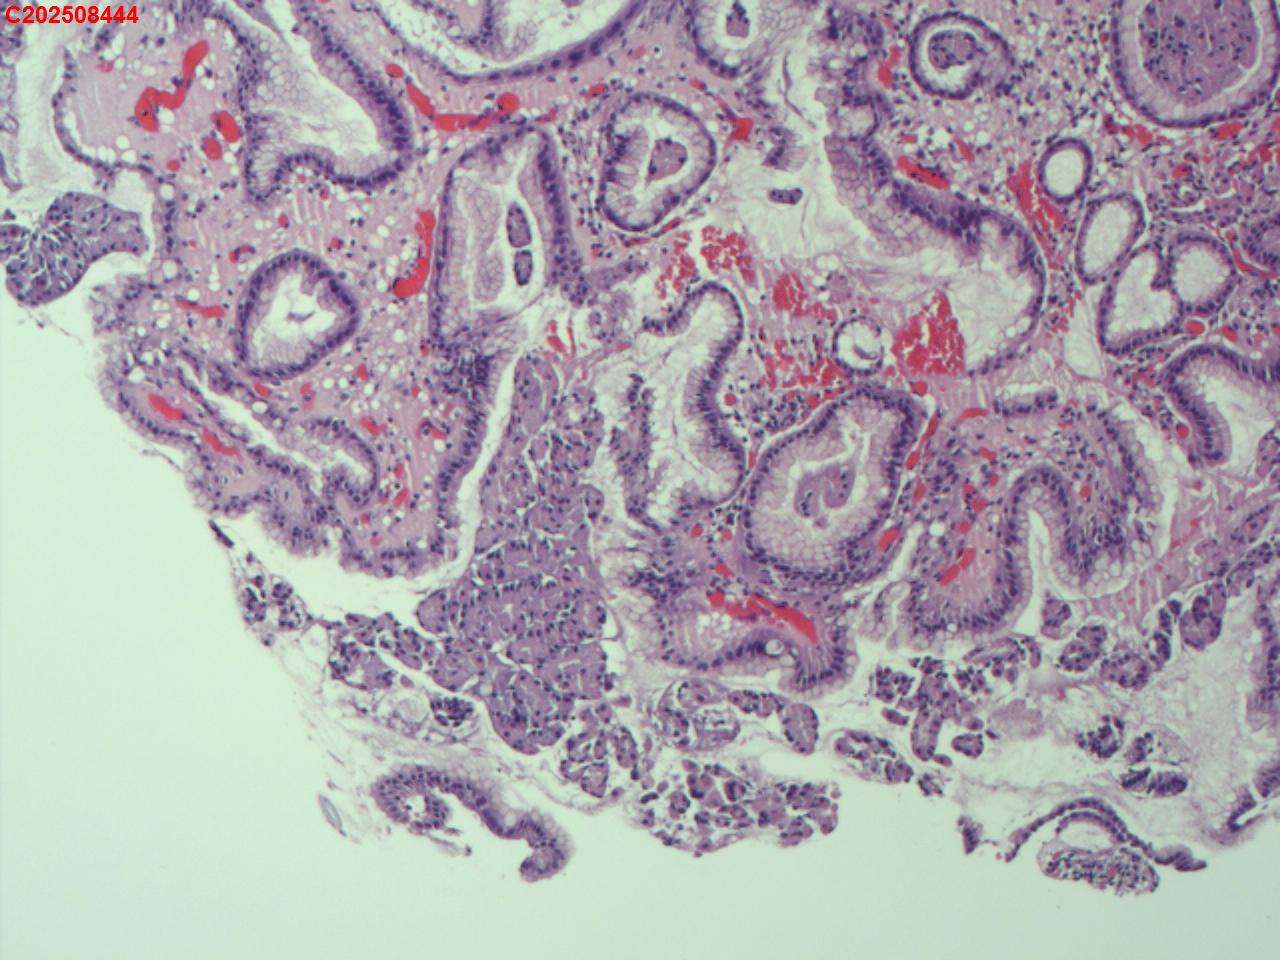

胃体可见多发直径2mm息肉,稍隆起,圆丘形

图4

增生性息肉

符合增生性息肉。